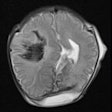

Postmortem MRI measures up for fetal autopsy

MRI shows babies feel pain like adults

Consent problems hold back fetal autopsies